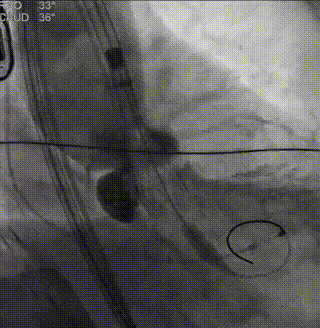

术前主动脉根部造影

导丝跨瓣

球囊预扩张